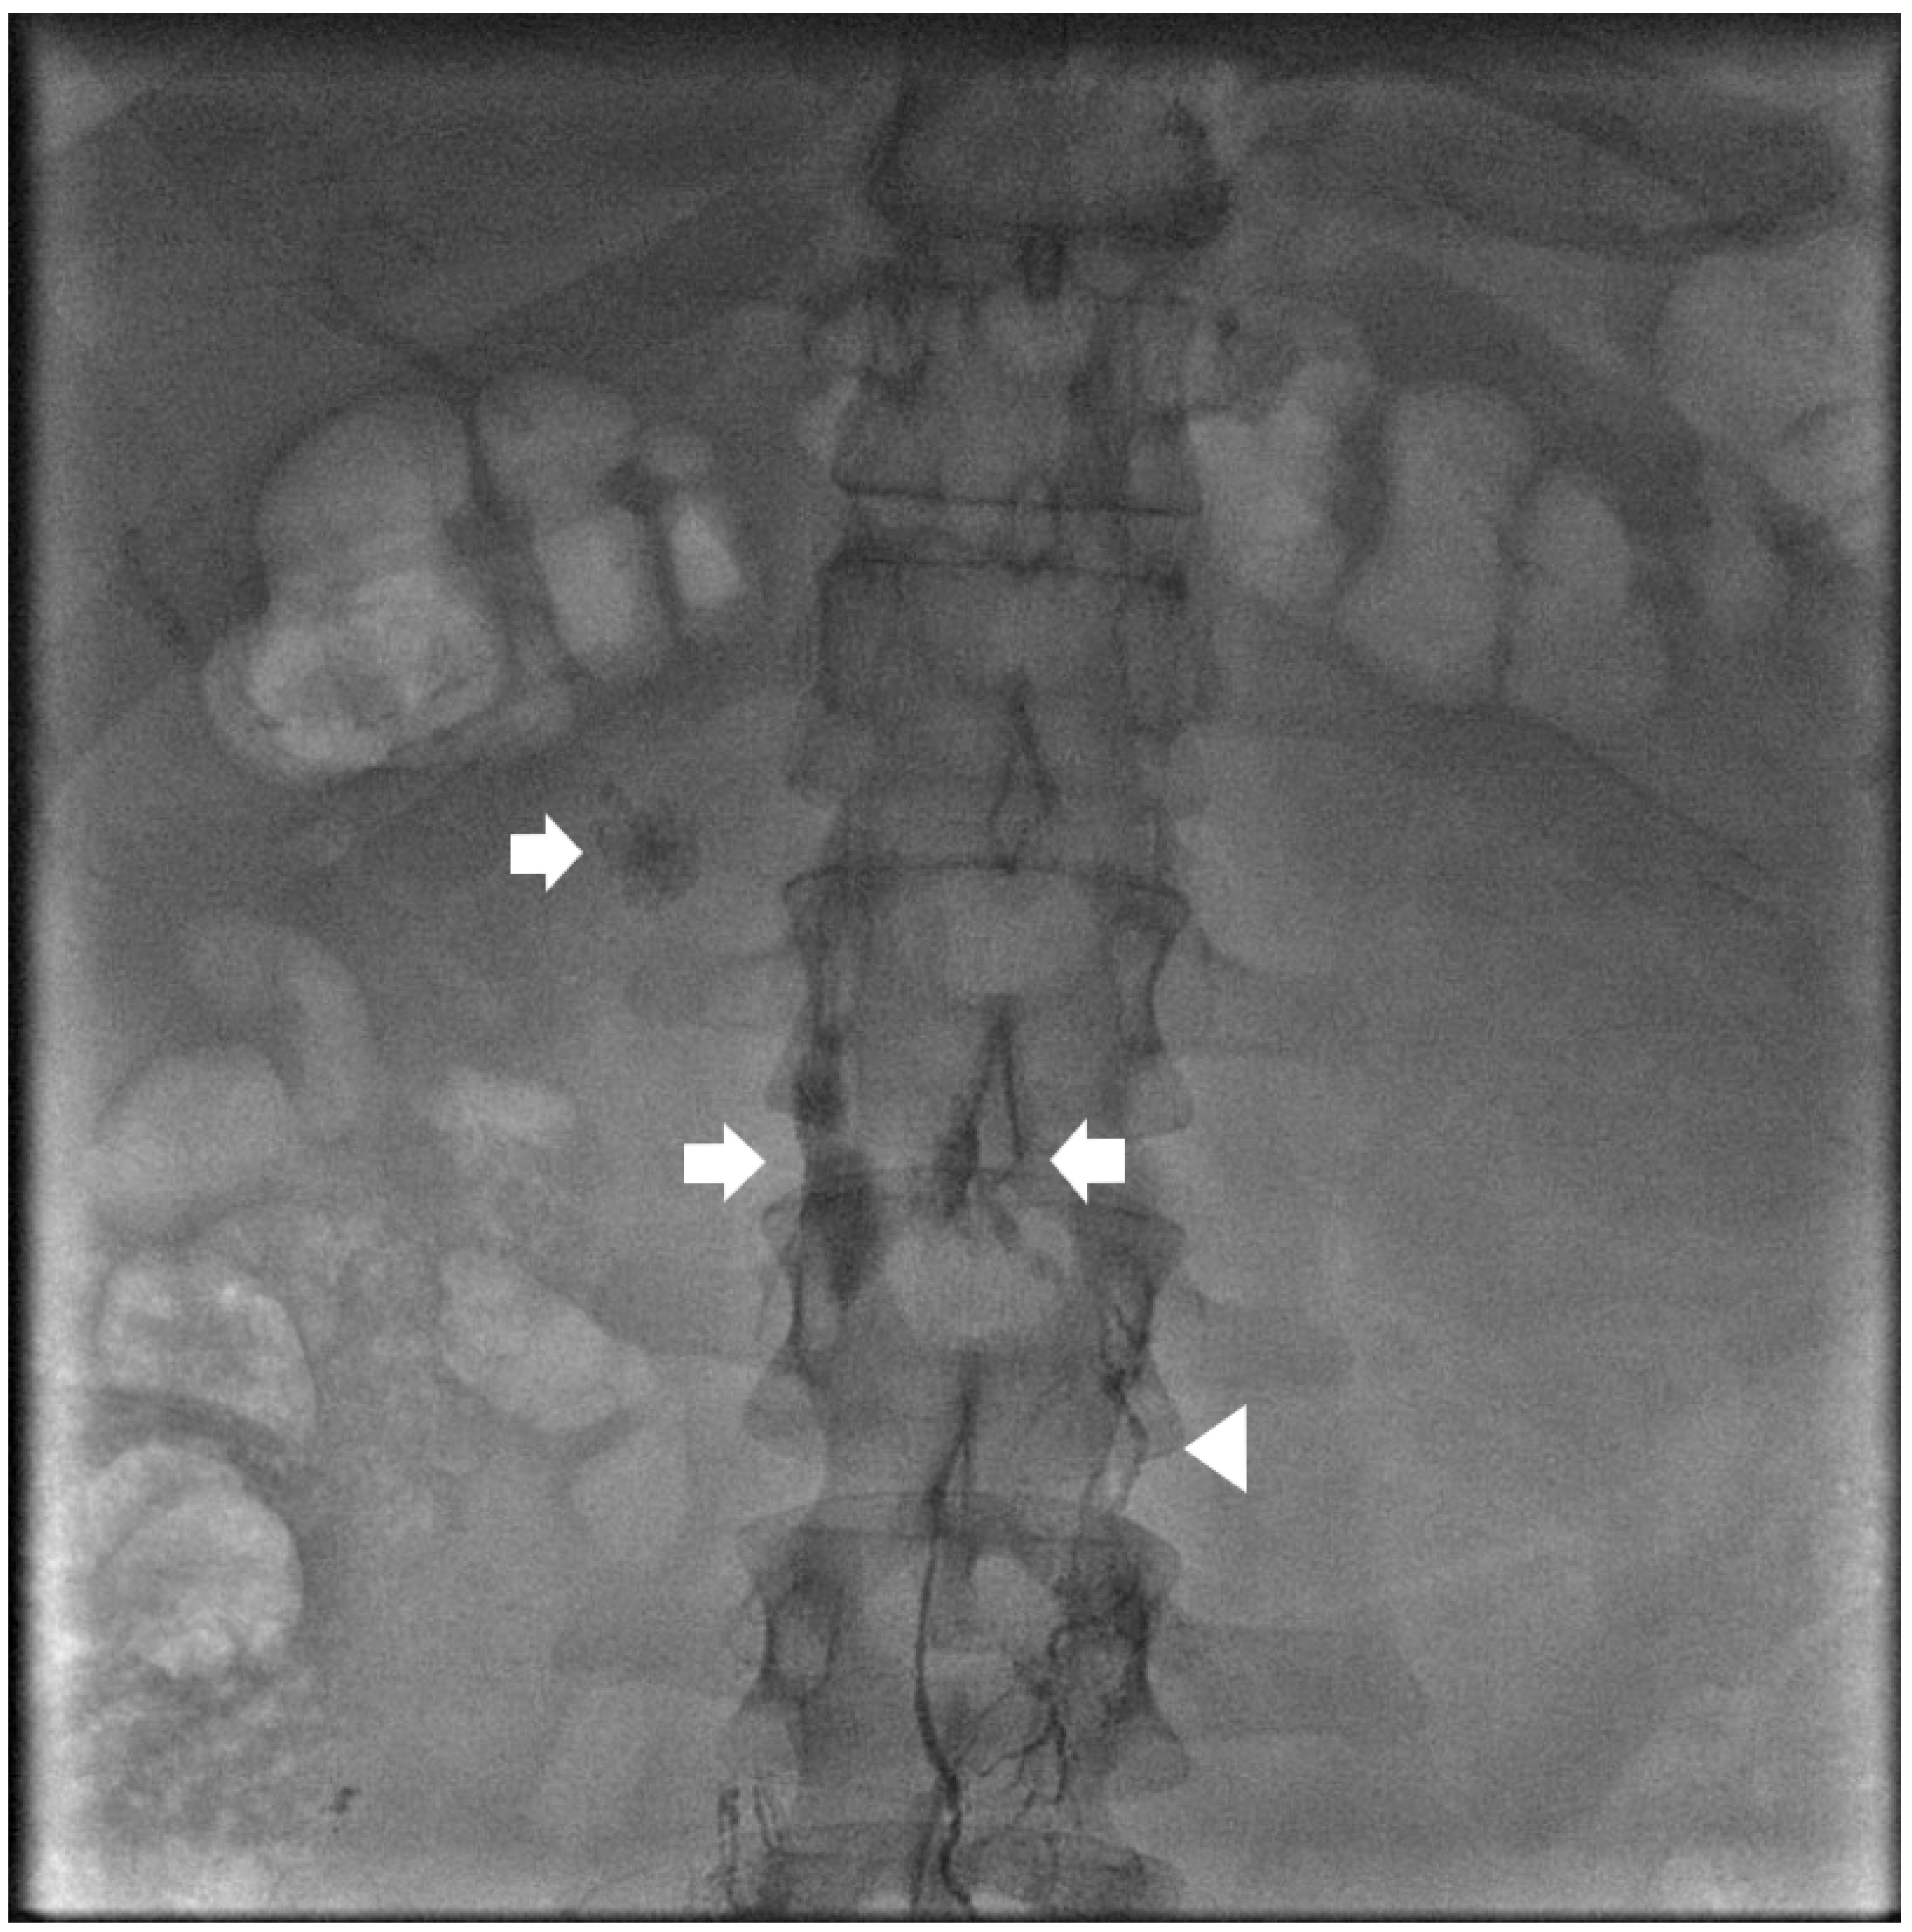

Management strategies for chylous ascites (CA) encompass a range of interventions, with a growing trend towards minimally invasive techniques. Intranodal lymphangiography (INL) is a primary management step for chylous ascites (CA) following conservative treatment failure. The procedure involves directly injecting contrast material (typically lipiodol) into lymph nodes to visualize the lymphatic system. INL serves as both a diagnostic tool and a potential standalone treatment (Figure 1). Aly et al. employed a conventional bilateral lymphangiography approach, using a minimum of 6 mL of lipiodol on each side [20]. This contrast with other studies using larger volumes, such as Verhaeghe et al., who reported a mean of 29.8 mL using it as the only treatment agent [21]. The technical success of INL is consistently high, approaching 100% in most studies. Technical success is generally defined as successful needle introduction and subsequent lymphatic opacification. However, injection methods, rates, dilution, and quantities of lipiodol vary among practitioners, reflecting the lack of standardization in CA management.

Figure 1.

Spot image from an intra-nodal lymphangiogram for a 39-year-old patient with traumatic chylous ascites after retroperitoneal lymph node dissection. Lipiodol is seen filling the retroperitoneal lymphatics (arrowhead) and leaking into the peritoneal space (arrows).